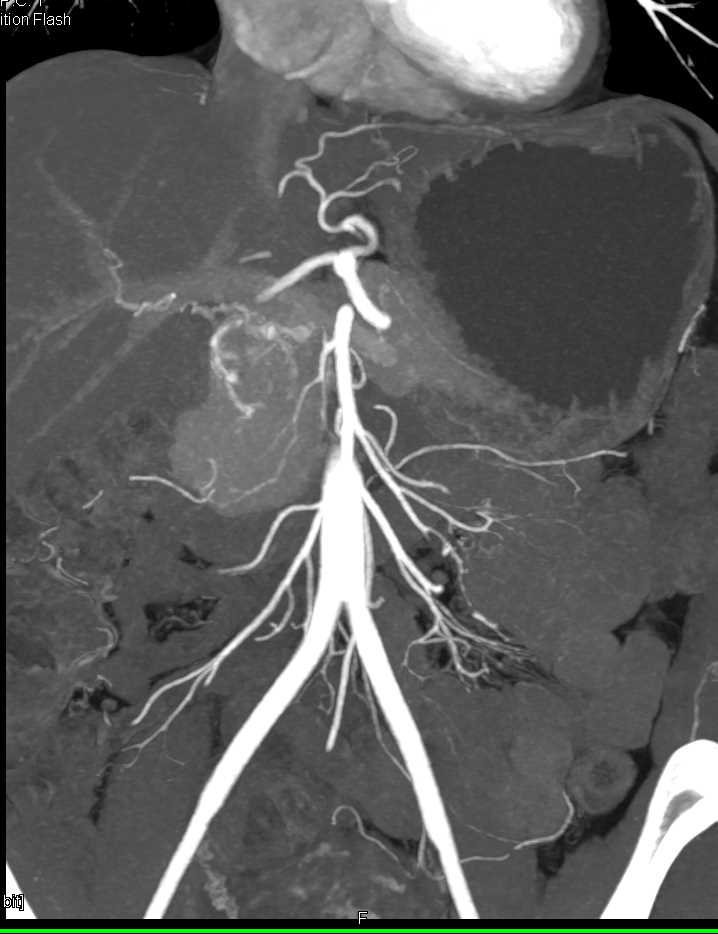

Subtle Pancreatic Cancer with Obstruction of Pancreatic Duct